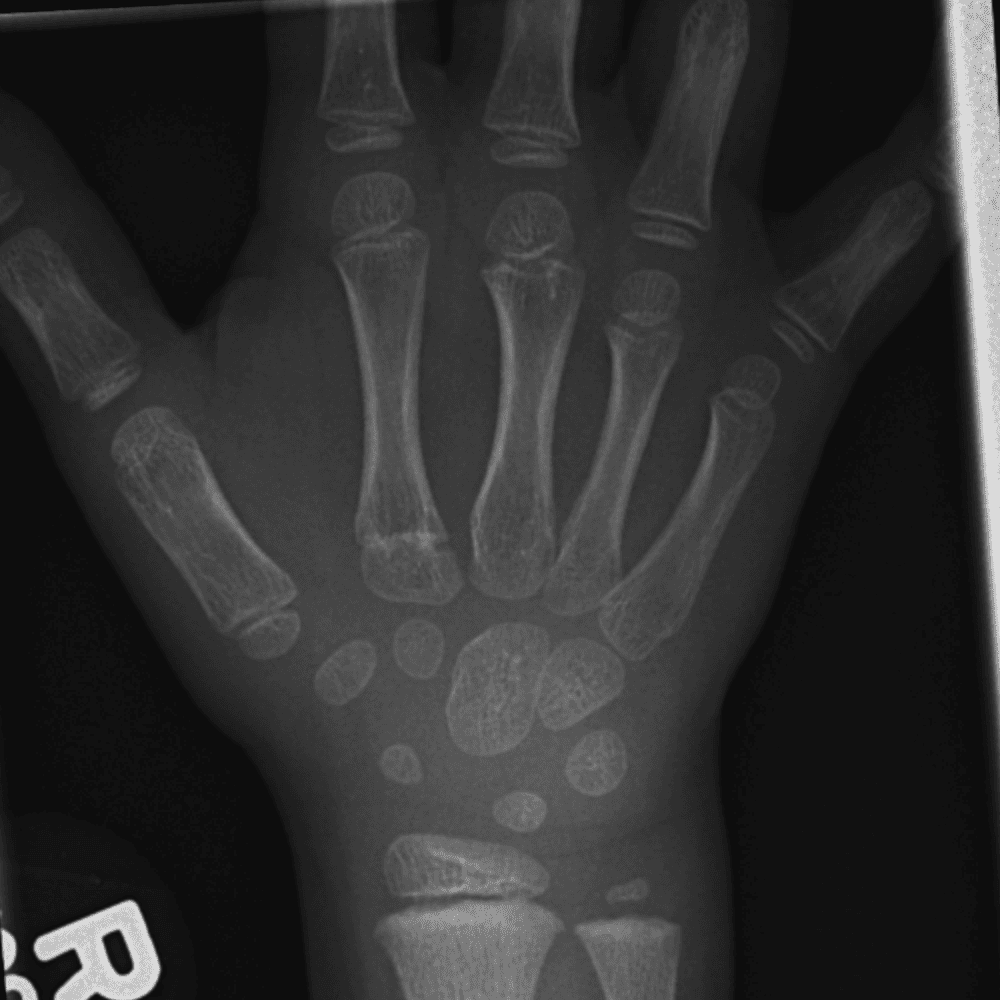

Simulates call by including subtle or difficult cases and some normals.

30 cases